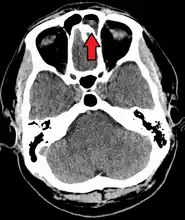

CT of chronic sinusitis -

CT scan of chronic sinusitis, showing a filled right maxillary sinus with sclerotic thickened bone. -